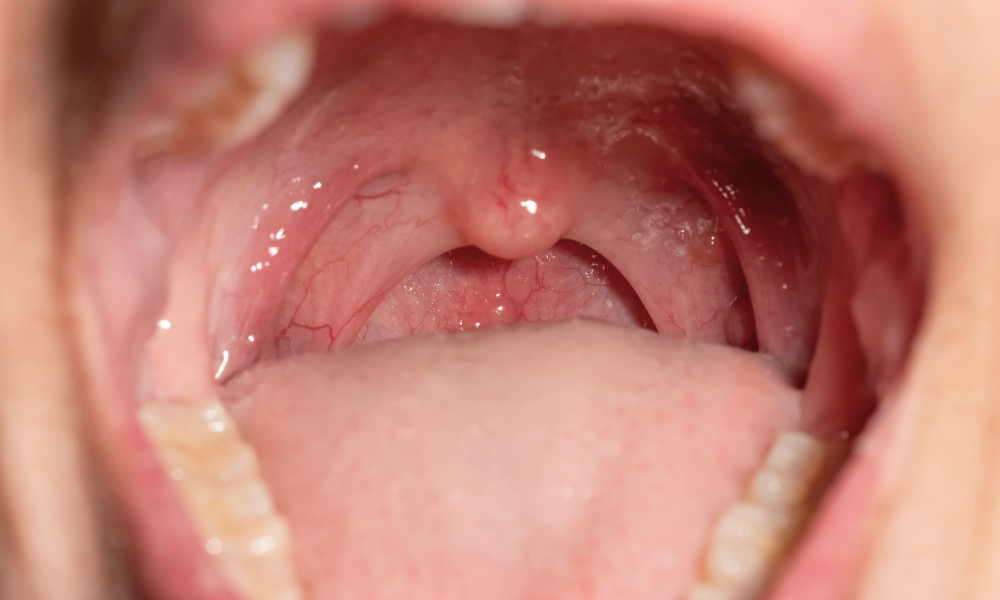

Treći krajnik (adenoid) predstavlja limfno tkivo smešteno u gornjem delu ždrela, koje kod dece može biti uvećano i izazvati niz tegoba: otežano disanje na nos, hrkanje, česte infekcije gornjih disajnih puteva, sekreciju iz nosa, pa čak i probleme sa sluhom i govorom.